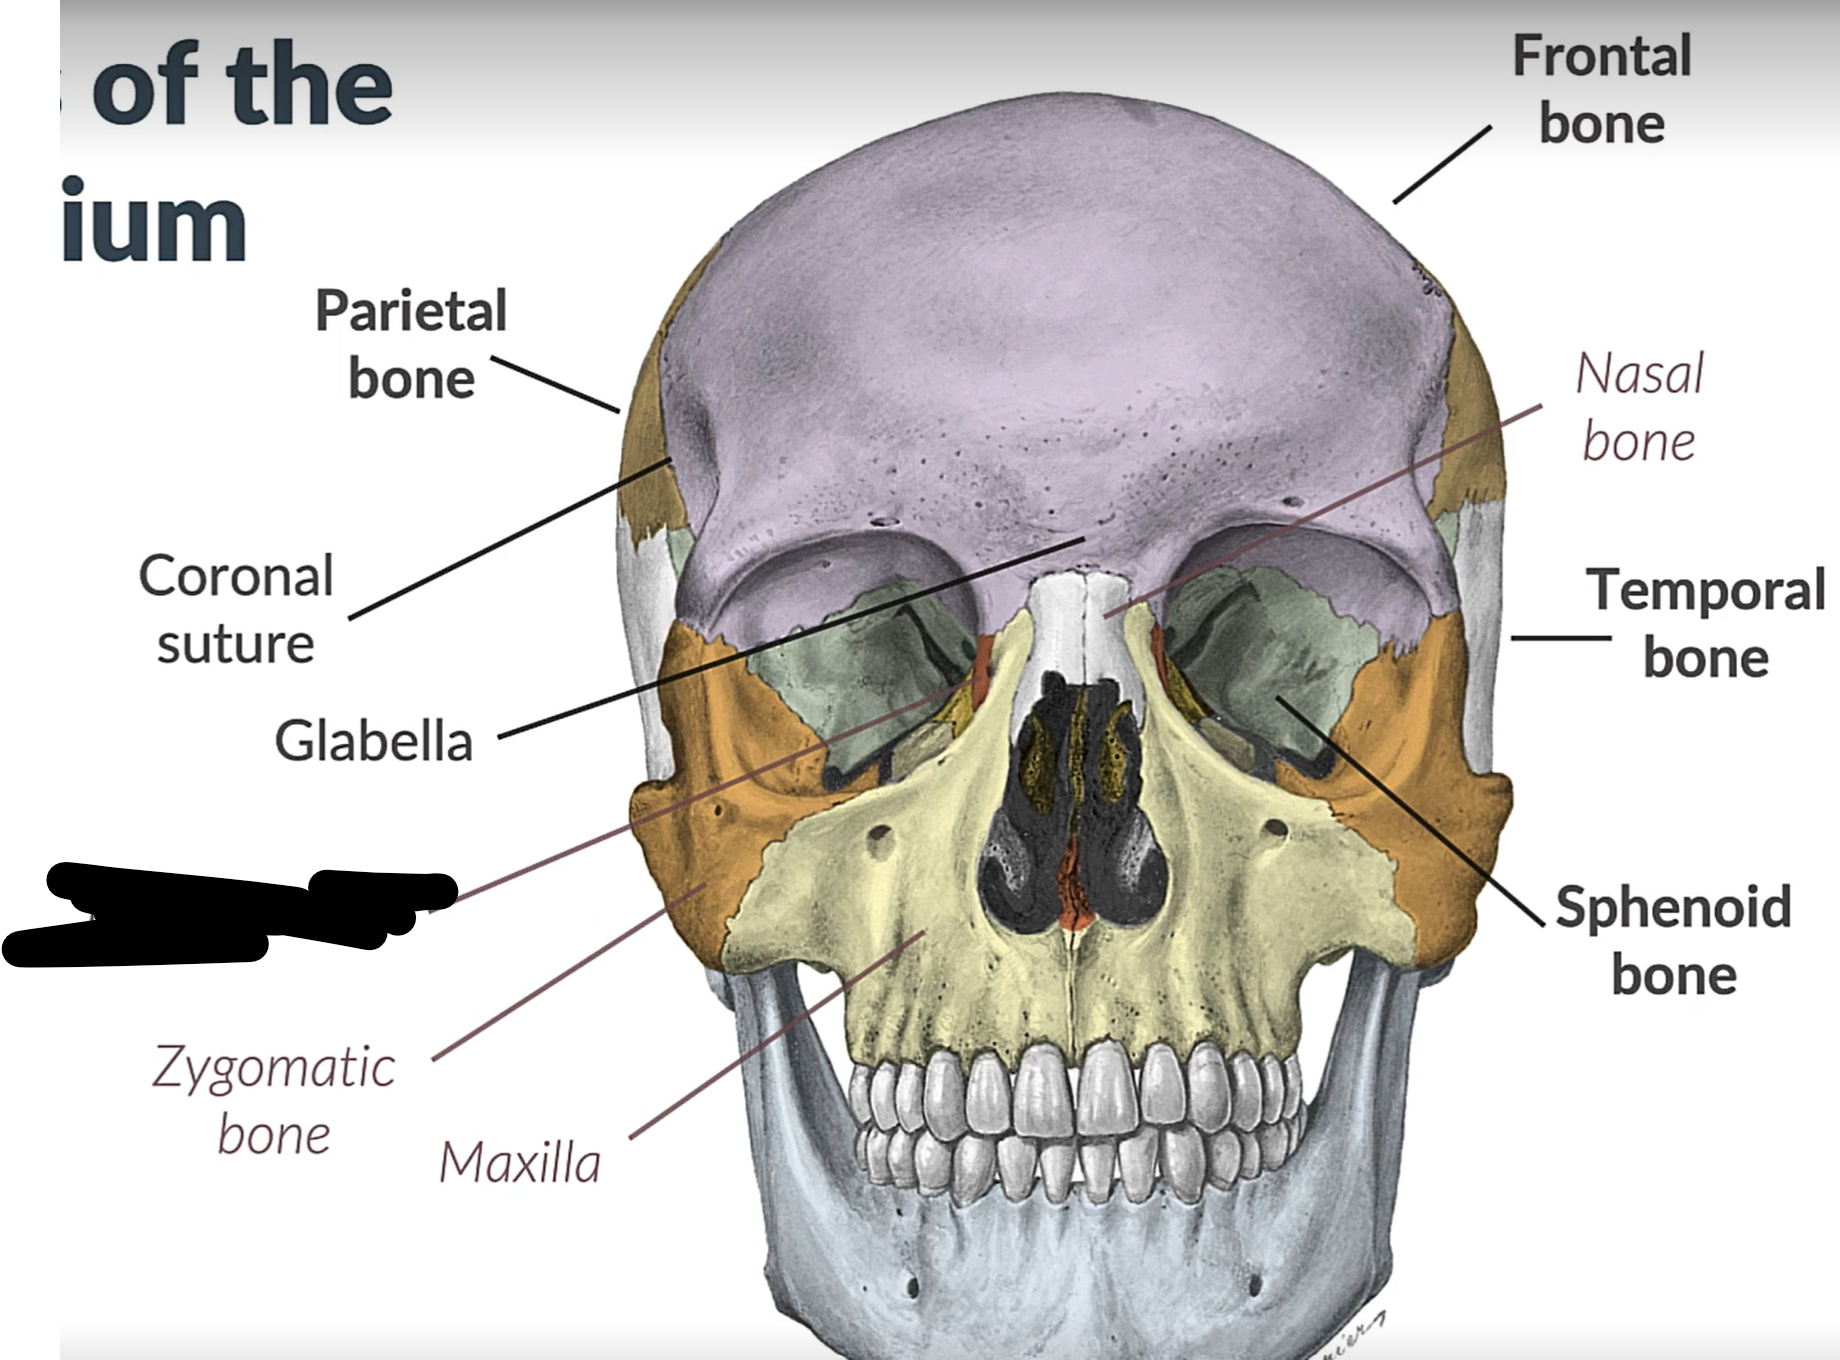

Parietal bone

Frontal bone

Temporal bone

Sphenoid bone

Zygomatic bone

Lacrimal bone

Coronal suture

Maxilla